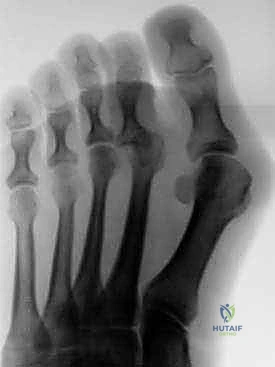

يعتمد الدكتور هطيف على التقييم السريري الشامل. يقوم بفحص القدم أثناء الوقوف والمشي والجلوس. يتم اختبار "مرونة" التشوه بدقة. بالإضافة إلى ذلك، يتم طلب صور أشعة سينية (X-rays) بوضع الوقوف (Weight-bearing) لتقييم حالة العظام، زوايا المفاصل، واستبعاد وجود التهاب مفاصل تنكسي أو خلع جزئي في المفصل المشطي السلامي.